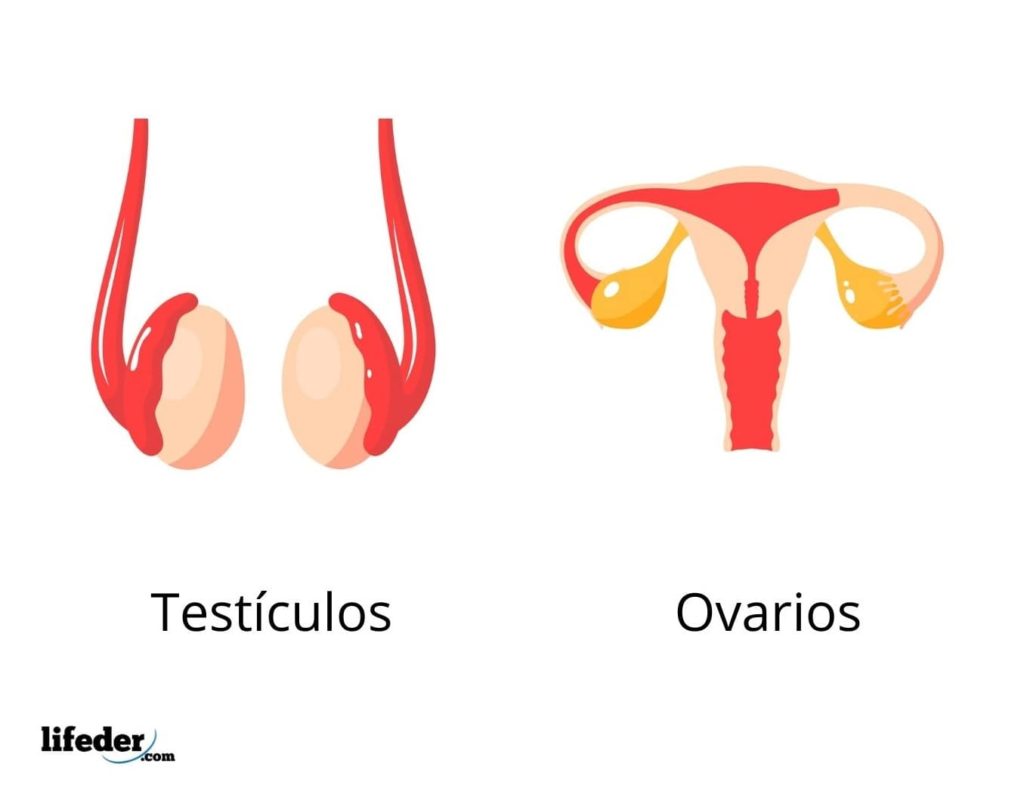

Estas glándulas se encargan principalmente de la liberación de hormonas, las cuales son distribuidas hacia los distintos órganos “diana”. Las glándulas endocrinas más importantes del cuerpo son las glándulas suprarrenales o adrenales, la hipófisis, la tiroides, la paratiroides y la glándula pineal, los ovarios, la placenta y los testículos.

– Los ovarios, la placenta y los testículos se encargan de la secreción de hormonas “sexuales” que influyen sobre el desarrollo de los órganos sexuales y por ende, sobre la definición del sexo y la reproducción.

Es importante destacar que algunas glándulas del cuerpo humano son mixtas, lo que en otras palabras quiere decir que poseen porciones endocrinas y porciones exocrinas, ejemplo de las mismas son el páncreas, los testículos y los ovarios.